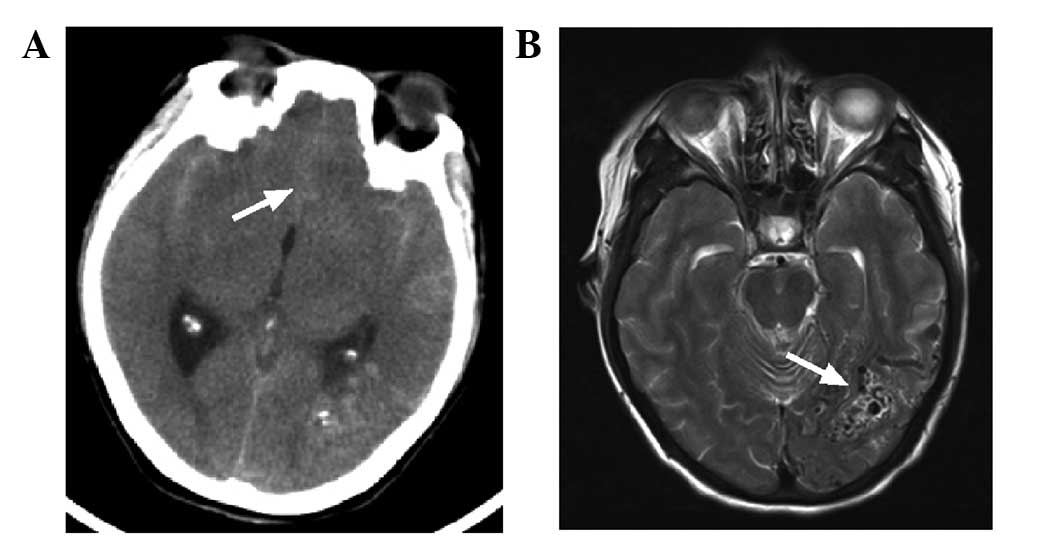

Following admission, a head computed tomography (CT) scan (SOMATOM Definition AS; Siemens AG, Munich, Germany) revealed a high-density cord-like shadow in the suprasellar cistern, the ambient cistern and the lateral Sylvian cistern, and a high-density calcification in the left occipital lobe, whereas the bilateral ventricles were of normal size. Magnetic resonance imaging (MRI; MAGNETOM Trio, A Tim System; Siemens AG) showed a flow-void signal in the left occipital lobe, suggesting AVM (Fig. 1). In addition, MRI revealed a mass of tortuous vessels in the left occipital lobe, and the branch of the left posterior cerebral artery was observed passing into the lesion, with an observable bent and inappropriately shaped draining vein. The bilateral middle cerebral artery and the right anterior cerebral artery A1 segment were abnormally displayed, and an abnormal vascular network was observed in the area that the bilateral middle cerebral arteries supplied to, suggesting MMD; the left anterior cerebral artery was clearly observable, and a berry-like projection was observed at the anterior communicating artery (Fig. 2). CT angiography (CTA; SOMATOM Definition AS) showed the presence of an AVM in the blood supply near the left middle cerebral artery and the posterior cerebral artery, and the draining vein converged into the superior sagittal sinus upward and the transverse sinus backward. An aneurysm was observed in the anterior communicating artery, with a size of ~4.6×4.2 mm, projecting to the lower right side (Fig. 3). A digital subtraction angiography (DSA; Siemens Neurostar Plus; Siemens AG) examination of the intracranial arteries was performed to confirm the diagnosis of MMD, the presence of AVM in the left occipital lobe, and the anterior communicating artery aneurysm (Fig. 4). Intracranial magnetic resonance perfusion imaging (MRP; MAGNETOM Trio, A Tim System) was performed, following the injection of gadolinium-DTPA (0.1 mmol/kg; Omniscan™; GE Healthcare Bio-Sciences, Pittsburgh, PA, USA) into the patient. Cerebral blood volume (CBV), cerebral blood flow (CBF), mean transit time (MTT) and time to peak (TTP) were measured by comparing the bilateral colors and time parameters; these results showed that the CBV, CBF, MTT and TTP were symmetrical in the bilateral hemispheres and that there were no significant ischemic changes in the brain tissue (Fig. 5).

Figure 1.

CT and MRI imaging of the head of the patient. (A) CT scan showed a high-density cord-like shadow in the lateral Sylvian cisterns and the longitudinal Sylvian (white arrow), suggesting a subarachnoid hemorrhage. (B) MRI scan revealed a flow-void signal in the left occipital lobe (white arrow), suggesting arteriovenous malformation. CT, computed tomography; MRI, magnetic resonance imaging.